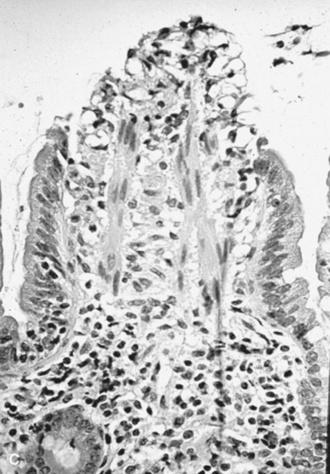

BIOPSY

The decision about whether to obtain a biopsy is often based on the ease of obtaining a sample and the relative value of the evaluation that can be made. Very small samples, such as those obtained with an endoscope biopsy instrument, are relatively easy to obtain, but they provide limited information. Full-thickness bowel specimens, obtained by means of ventral midline or flank laparotomy, are more difficult to obtain, but they provide much more information.

Taking a biopsy sample by endoscopy allows the practitioner to choose the biopsy site on the basis of the appearance of the mucosal surface, which most frequently reflects an inflammatory disorder. Conversely, when a biopsy sample is obtained through laparotomy, the serosal surface of the bowel may not reflect a disorder within the bowel wall. In such instances it may be useful to obtain several biopsy specimens. Rectal mucosal biopsies are easily performed. Many instruments can be used to obtain the biopsy specimen, and a uterine biopsy forceps works well. A fold of mucosa can readily be pinched between two fingers, and a sample of this tissue is obtained. The size of the sample is adequate for histologic or bacteriologic examination.

Maldigestion tests are performed to evaluate exocrine pancreatic function and small intestinal mucosal brush border disaccharidase activity. Pancreatic exocrine deficiencies have not been described in the horse, probably because equine pancreatic secretions consist primarily of water and bicarbonate and have less enzymatic activity than in monogastric omnivorous species. Mucosal brush border disaccharidase-related maldigestion is relevant in viral and bacterial enteritides of foals, particularly rotavirus and coronavirus enteritides. As a result of these viral infections, there is loss of the superficial villous epithelial cells of the small intestine, in which the disaccharidases lactase, cellobiase, maltase, sucrase, and trehalase are located.34 Lactase levels are greatest in young suckling foals, and loss of this enzyme activity, secondary to loss of the mucosal villous cells, leads to lactose maldigestion. Lactose tolerance can be tested by administering a 20% solution of D-lactose at a dose of 0.5 to 1 g/kg. This dose should result in an approximate doubling of the serum glucose level within 60 minutes of administration.35